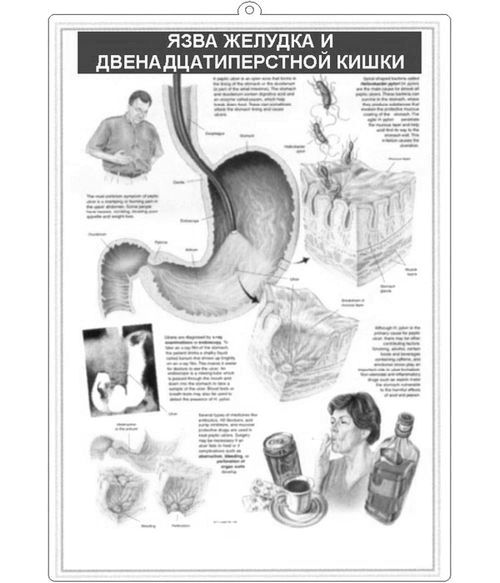

Всі види гастритів досить серйозні захворювання, які, якщо їх не лікувати, можуть привести до виразки шлунка.

Антральний ерозивнийгастрит - це, мабуть один з найпоширеніших видів. Це захворювання розвивається внаслідок проникнення в шлунок хелікобактер пілорі, мікроорганізму, який живе під слизом. Хелікобактер викликає запалення слизової оболонки шлунка, що призводить до неймовірним болів. Якщо нічого не робити і не лікувати даний вид гастриту Хелікобактер пілорі часто призводить до виникнення раку шлунка.

Гострий гастрит зустрічається рідко, він в основному буває у тих людей, які навмисно або випадково вживають отрутохімікати або будь-які кислоти. Гострий гастрит розвивається стрімко, як правило уражається вся слизова оболонка шлунка, але самі виразки неглибокі. Це найважчий і страшний вигляд гастриту.

Через неправильного способу життя, через нерегулярне харчування і пристрасті до шкідливих звичок в організмі людини розвивається геморагічний або хронічний гастрит. Виразки досягають від 3 до 7 мм в діаметрі. Це найбільш поширений вид гастриту.

Ерозивний рефлюкс гастрит виникає через те що в шлунок потрапляє вміст 12-палої кишки. Це в основному призводить до набряку і утворення виразок.

Для того щоб визначити який тип гастриту у пацієнта необхідно пройти обстеження:

- Ендоскопія. У стравохід, а потім у шлунок вводиться спеціальний зонд (ендоскоп), завдяки якому проводиться дослідження слизової оболонки шлунка. Спеціально з місця виразки відщипується шматочок тканини, який потім відправляють на дослідження, на наявність Хелікобактер пілорі.

- Загальний аналіз крові. Анемія також є характерною ознакою ерозивного гастриту.

- Аналіз калу на приховану кров.

Звичайно, ставити самому собі діагноз при наявності декількох симптомів не варто, але все, ж необхідно відразу ж звернутися до лікаря-гастроентеролога якщо є такі симптоми:

Це основні ознаки хронічного гастриту, які, на жаль, з'являються вже в запущеному стані, так як геморагічний гастрит в основному проходить безсимптомно.

Для гострого гастриту характерні такі симптоми:

- Блювота, часто з кров'ю

- нудота

- Тупий ниючий біль в шлунку відразу ж після прийому їжі

- печія

- Нестабільний стілець, іноді з кров'ю

Симптоми гострого гастриту виникають раптово, а саме захворювання розвивається стрімко.

Для визначення різновиду гастриту насамперед проводять ендоскопію. Потім в обов'язковому порядку проводяться дослідження крові і калу. При важкій діагностиці іноді вдаються до рентгенологічного дослідження.

Першим етапом медикаментозного лікування є потужна атака антибіотиками, якщо лікується гастрит, викликаний хелікобактер пілорі. В основному призначають антибіотики групи кларитроміцину, левофлоксацину, тетрацикліну або амоксициліну. Ці препарати необхідно приймати повний курс, який призначить лікар, ні в якому разі не можна різко припиняти прийом препаратів, так як це викличе швидке зростання мікроорганізмів.

Спеціальна дієта - це відмова від гострих, копчених, солених, жирних, маринованих страв. Крім того необхідно прибрати зі свого раціону солодкі страви, випічку на дріжджах. Виключити прийом фруктів і овочів, які підвищують кислотність, наприклад цитрусові.

Для того щоб загоєння виразок проходило швидше найкраще пити смачні трав'яні чаї або ж заварювати не міцний зелений чай. Ранок, яке починається з кухлика ароматного фіто чаю або зеленого чаю принесе заряд бадьорості та енергії краще, ніж кава або кофесодержащіе напої. Для тих, хто курить чи часто запиває їжу алкоголем, слід назавжди прибрати зі свого життя ці звички. Здоров'я важливіше.